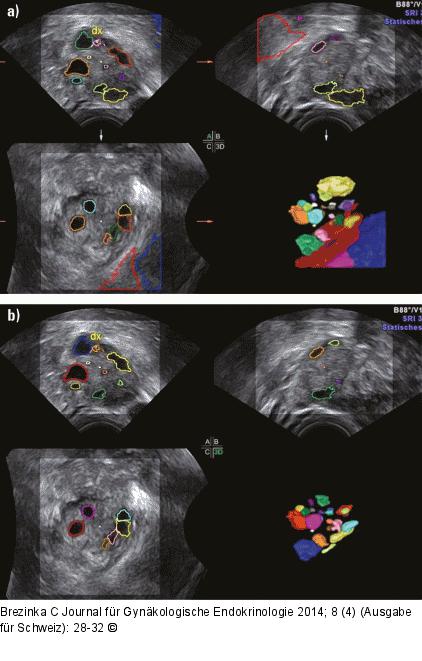

Abbildung 5a-b: Follikelmessung „Wegklicken“ falsch aufgenommener Strukturen: (a) Im 3D-Bild befinden sich unten rechts eine rote, eine blaue und eine lila Struktur, die sicher nicht dem Ovar zuzuordnen sind. (b) Nach vorheriger Markierung und Druck auf die obere Trackballtaste wird jede dieser Strukturen weggeklickt, woraufhin ein plausibles 3D-Bild entsteht. Die Farben sind nun anders vergeben. |

Abbildung 5a-b: Follikelmessung

„Wegklicken“ falsch aufgenommener Strukturen: (a) Im 3D-Bild befinden sich unten rechts eine rote, eine blaue und eine lila Struktur, die sicher nicht dem Ovar zuzuordnen sind. (b) Nach vorheriger Markierung und Druck auf die obere Trackballtaste wird jede dieser Strukturen weggeklickt, woraufhin ein plausibles 3D-Bild entsteht. Die Farben sind nun anders vergeben. |